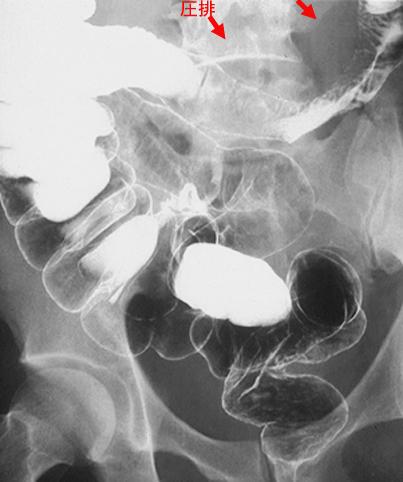

疾病(病理主体)的分类转移性肿瘤/

部位(按器官分)小肠/空肠

检查方法X线

肿瘤最大直径40以上